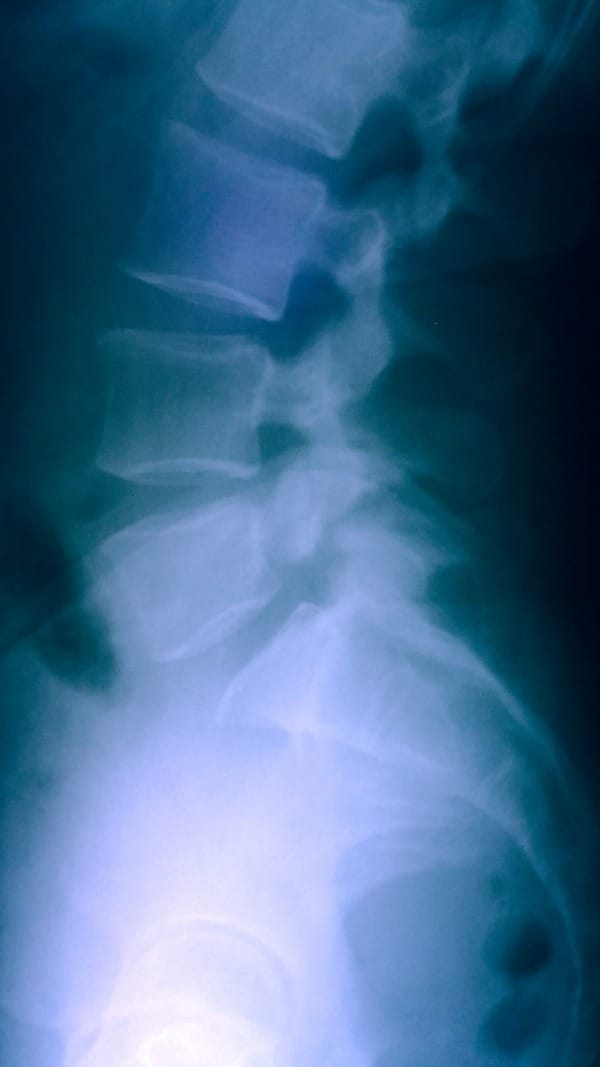

The radiographs revealed a much more concerning issue. My L5 vertebrae is slipping forward (spondylolisthesis) and the vertebrae’s pars interarticularis is broken/fractured (spondylosis). My L5 is separating from my S1.

Most of the exercises and chiropractic care I have done and received over the years are not recommended as they could and most likely did make my condition worse.

Both my chiropractor and physical therapist thought an accident involving a hard fall to my spine must have caused the spondylolisthesis and spondylosis. I remember a few falls, but none that I would consider hard enough to cause this condition. The other suggestion is a possible degenerative genetic condition. Since we cannot conclude the cause, we are simply moving ahead to the treatment and management.

Physical therapy focusing on core therapy will help support my sliding and broken vertebrae. Not just any exercises, but ones specifically designed for my situation. I will need to do them for the rest of my life to avoid spinal surgery. This will not cure the condition but will control it from worsening.